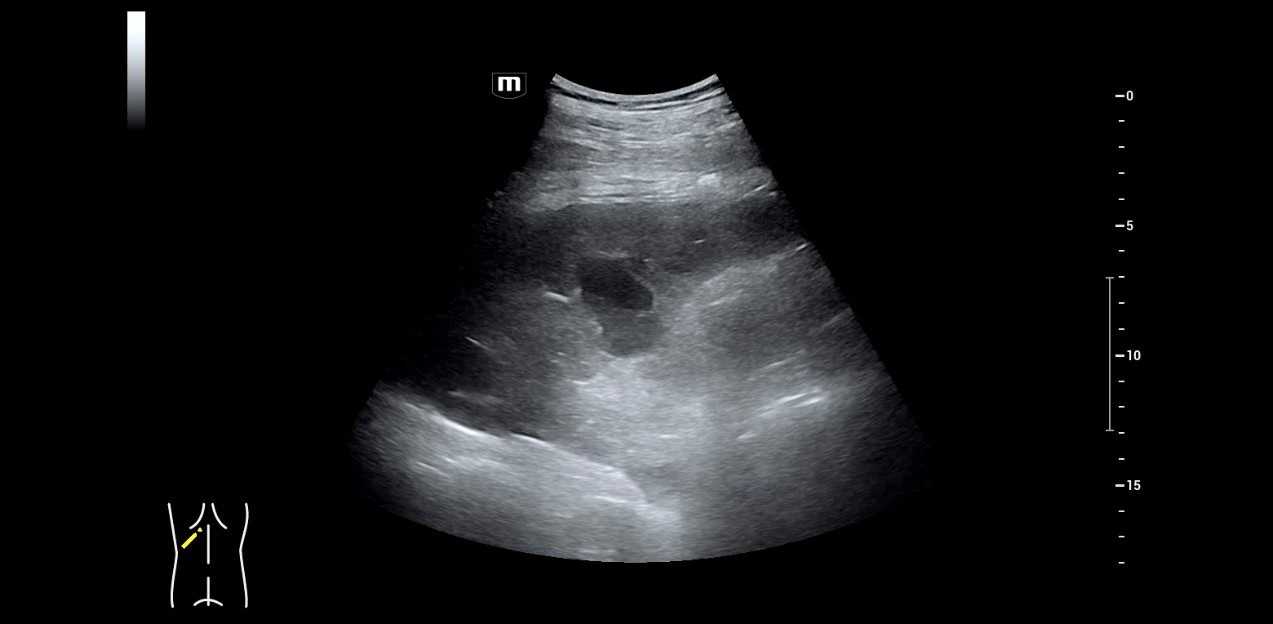

FÞr das Resona I9 hat sich Dr. Seibel aus verschiedenen GrÞnden entschieden. Zun?chst einmal, weil das High-End-Ger?t neben einer ausgezeichneten Bildqualit?t mit hoher Aufl?sung auch die M?glichkeiten zu fokussierten Untersuchungstechniken bietet, die ihm die Diagnosestellung erleichtern. So nutzt der Stationsleiter beispielsweise viel und gern den kontrastmittelverst?rkten Ultraschall (CEUS), um unklare Befunde abzukl?ren.